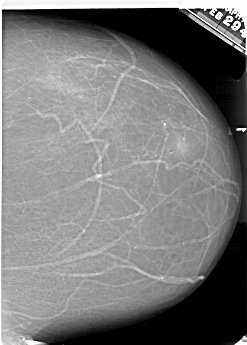

A_1701_1.LEFT_CC

LEFT_CC LINES 6691 PIXELS_PER_LINE 4756 BITS_PER_PIXEL 12 RESOLUTION 43.5 OVERLAY